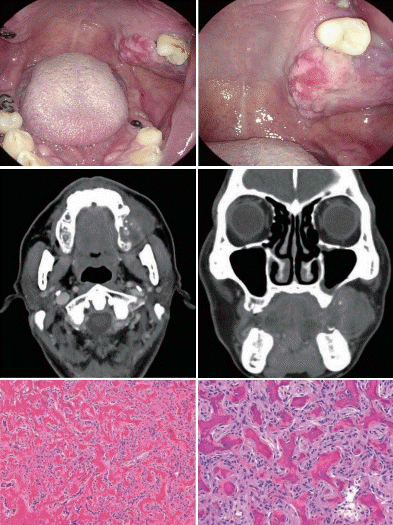

56세 남자가 3개월 전부터 인지한 구강 내 종괴가 서서히 커지고 통증이 발생하여 내원하였다. 주 1-2회 정도의 음주와 하루 1갑 정도의 흡연을 하고 있는 것 외에 특이병력은 없었다. 신체검진에서 좌측 상악 대구치의 일부의 탈락과 함께 잇몸에서 발생한 단단하고 고정된 종괴가 보이고, 표면은 미란과 궤양을 동반한 불규칙한 양상이지만 쉽게 출혈되는 양상은 아니었다. 경부에 촉지되는 림프절은 없었다. 외래에서 시행한 punch biopsy 결과 chronic inflammation with ulcer로 확인되었으며, 경부 CT 검사에서 약한 조영 증강의 혹이 일부 상악골 파괴 소견을 보이나 상악동 내로의 침범이 없었다. 심부 조직검사 결과 아래와 같은 양상을 보였다. 이 환자의 치료방법으로 가장 알맞은 것은?

해설 상치조암이 의심되지만 종괴의 특징 소견과 영상검사에서 골 파괴가 심하지 않고 약하게 증강 야상을 보이는 점, 일차 조직 검사에서 염증소견을 보인 점은 악성종양의 가능성이 낮아진다. 2차 조직검사 소견은 미성숙 뼈조직이 소주(trabecular) 양상을 띄고, 특이소견을 보이지 않는 간질세포(섬유아세포)가 둘러싸고 있는 양상으로 전형적인 ossifying fibroma (OF) 소견을 보여준다. OF는 주로 얼굴 뼈에 발생하는 양성종양으로 섬유성 이형증(fibrous dysplasia)과 감별하여야 하나, 병리적 특징상 비정상적 조골세포와 파골세포의 활동이 이루어져 재발이 흔하므로 정상 뼈 조직이 있는 곳까지 광범위 절제가 되어야 치료할 수 있다.